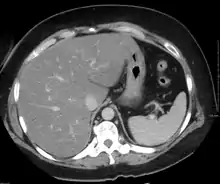

Liver steatosis (fatty liver disease) as seen on CT

Imaging studies are often obtained during the evaluation process. Ultrasonography reveals a "bright" liver with increased echogenicity. Medical imaging can aid in diagnosis of fatty liver; fatty livers have lower density than spleens on computed tomography (CT), and fat appears bright in T1-weighted magnetic resonance images (MRIs). Magnetic resonance elastography, a variant of magnetic resonance imaging, is investigated as a non-invasive method to diagnose fibrosis progression.[28] Histological diagnosis by liver biopsy is the most accurate measure of fibrosis and liver fat progression as of 2018.[6]